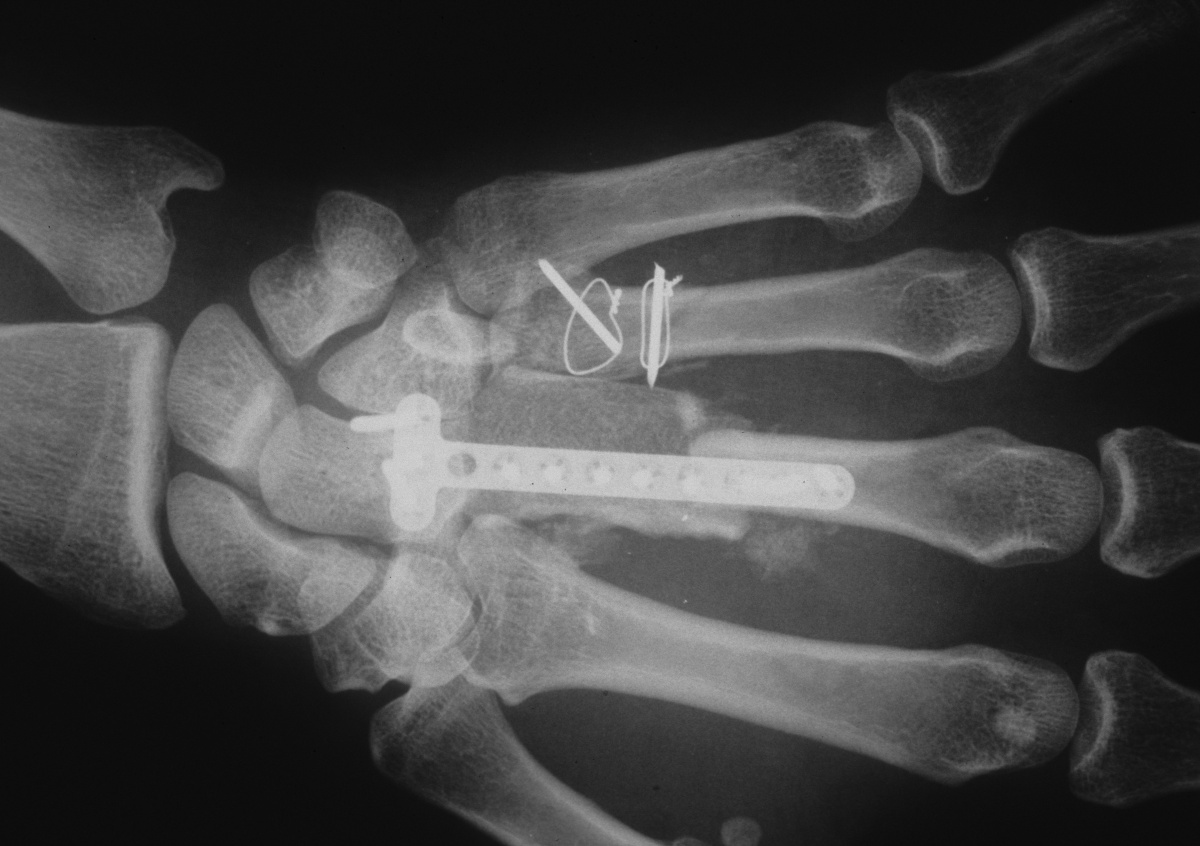

| Fixation of

bicortical iliac crest graft incorporating

carpometacarpal arthrodesis. |

| Three months

postop; bone graft incorporated, active motion

restored, recovery of sensation. |